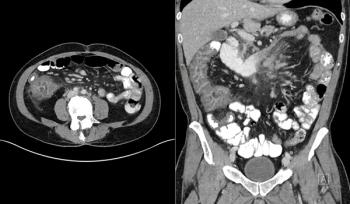

A 37-year-old man presents with a mass in the abdominal area. What is your diagnosis?